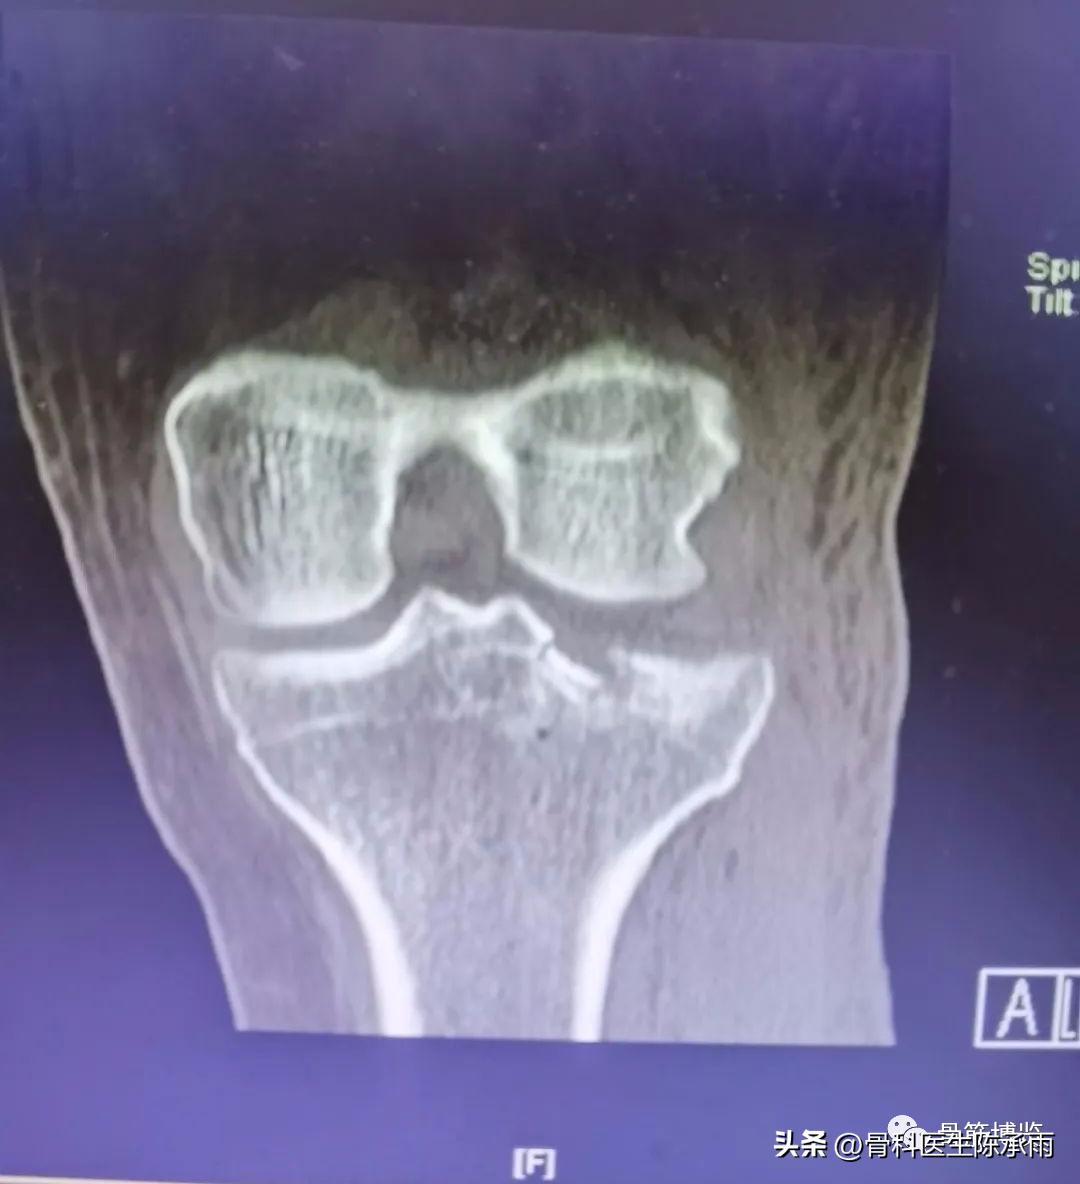

1例

2例

3例

4例

5例

6例

7例